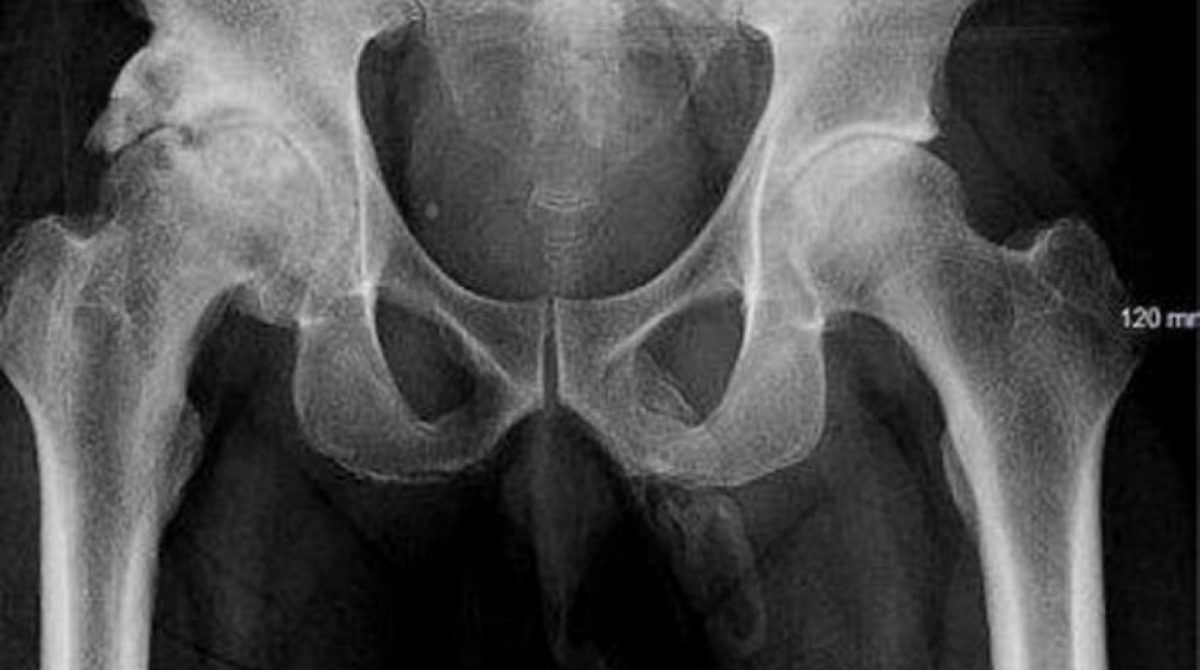

EUA - Um homem de 63 anos foi ao hospital após cair na rua e descobriu, depois de um exame de raio-x, que o seu pênis apresentava pontos de calcificação. As informações são do jornal 'Daily Mail'.

Médicos do Lincoln Medical Center, em Nova York, nos Estados Unidos, dizem que o paciente tem “células ósseas se formando dentro do membro”. Ao avisarem o idoso, ele se levantou e foi embora sem perguntar qual seria o tratamento recomendado.

Segundo os médicos, o caso é extremamente raro e com poucos registros médicos. “A ossificação do pênis continua sendo uma condição relativamente rara a ser mencionada em poucos periódicos da área, com menos de 40 casos registrados”, disse o médicos Georges El Hasbani.